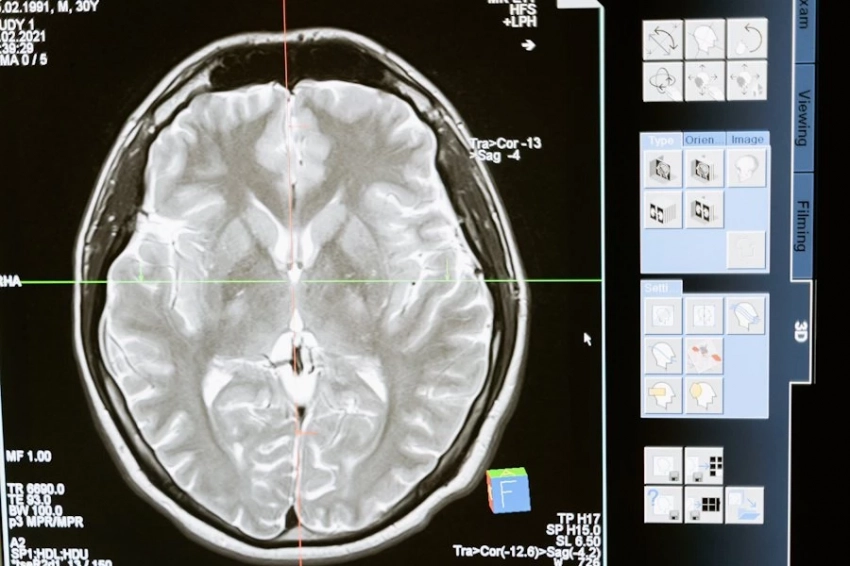

Фото из открытых источников Ученые из Нидерландов выяснили, что проблемы с чтением и письмом у детей, характерные для дислексии, могут быть связаны с генетическими особенностями. Открытие было представлено в журнале Science Advances. Дислексия характеризуется затруднениями в освоении навыков чтения и письма при сохранении общей обучаемости. К признакам расстройства относят сложности с чтением вслух, пониманием текста, беглостью чтения и правильным написанием слов. Причины могут быть связаны с